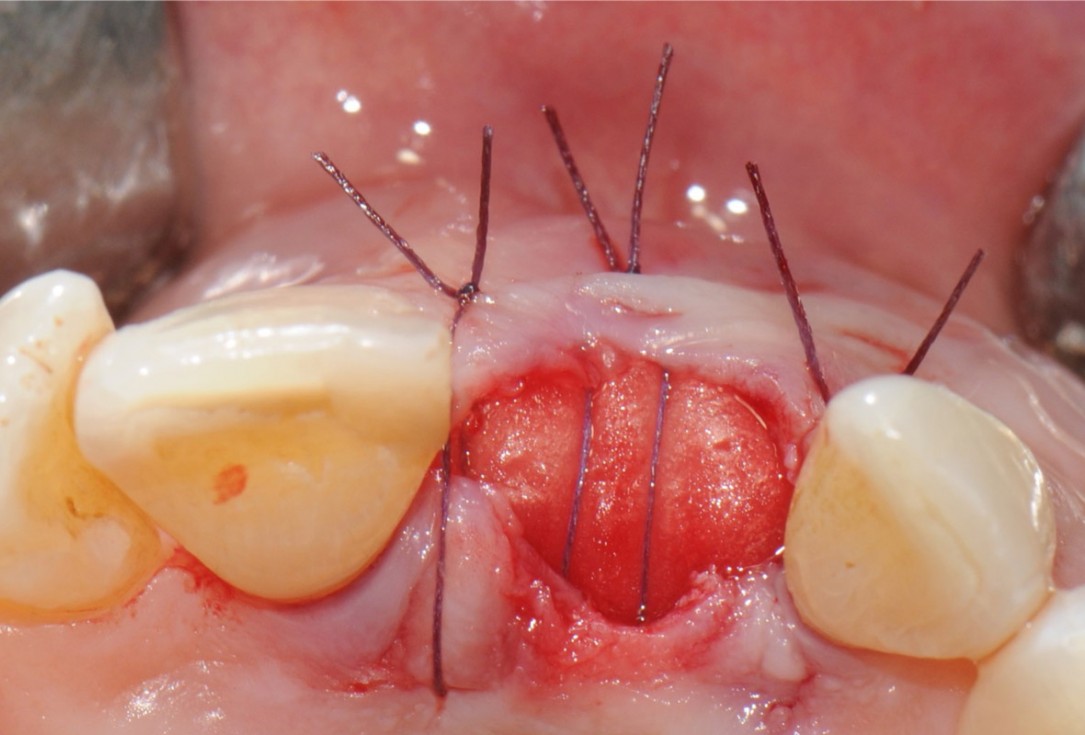

10/18 - Coverage of the socket with mucoderm® adapted to the alveolar morphology. 2/3 of mucoderm® surface is covered by mucosal flapTooth extraction and socket sealing with mucoderm® - Dr. A. Rossi

12/18 - Occlusal view of the wound closureTooth extraction and socket sealing with mucoderm® - Dr. A. Rossi